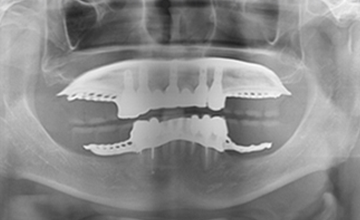

여러 개의 임플란트를 심은 뒤,

그 사이를 금속 막대로 연결해 튼튼한 지지대를 만들고,

그 위에 틀니를 안정적으로 고정하는 방식입니다.